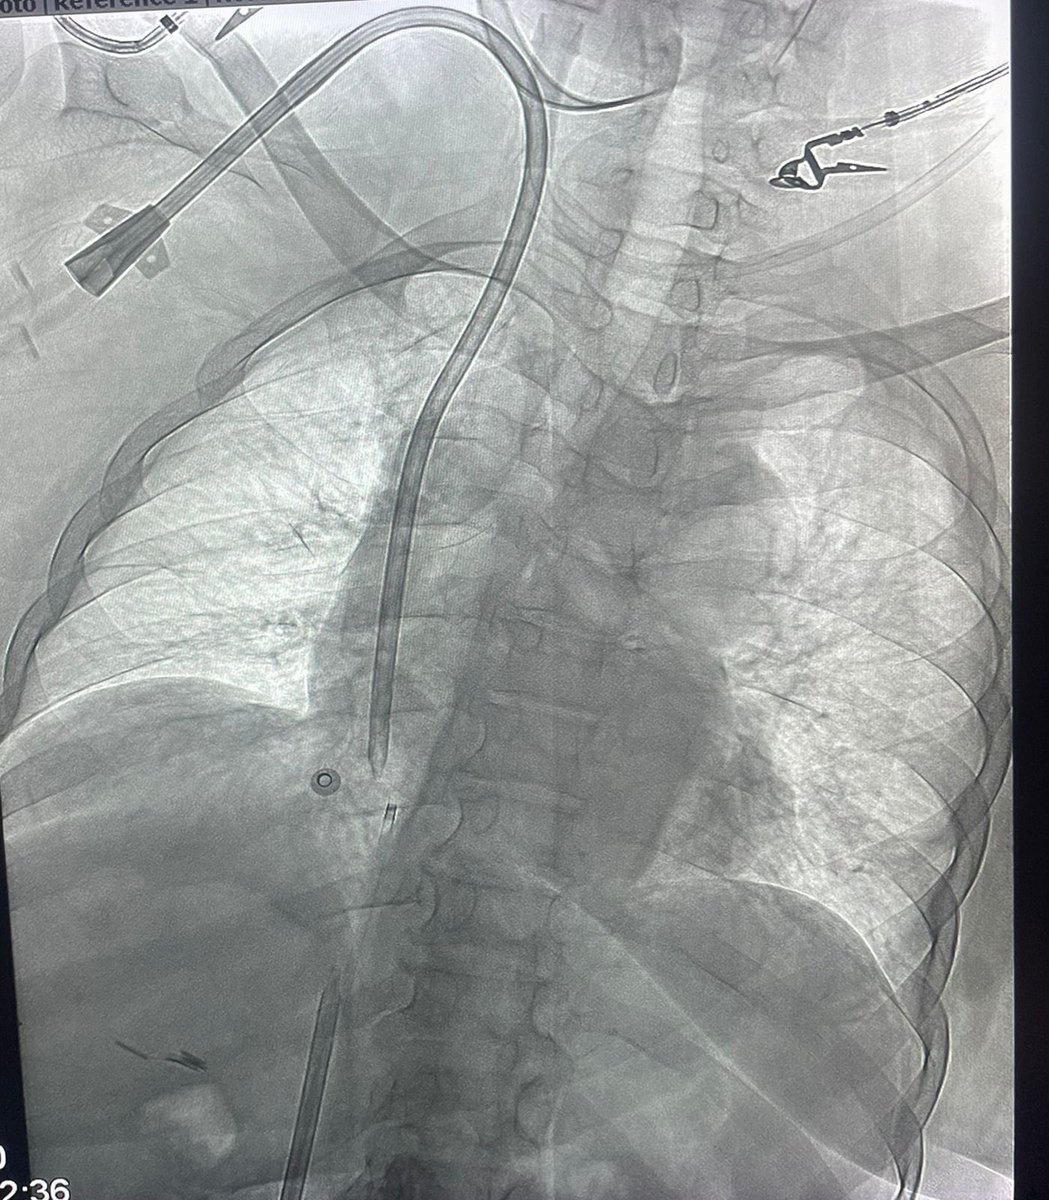

DLBCL with massive hemoptysis due COP. Bronchoscopy localized bleeding from the right. Right bronchial artery embolization was performed. What variance or aberrance have you personally encountered? Azzam Khankan عزام خانكان د. عبدالقادر القناوي @SalmanFelemban Majed Abdulhaq #InterventionalRadiology

DLBCL with massive hemoptysis due COP. Bronchoscopy localized bleeding from the right. Right bronchial artery embolization was performed. What variance or aberrance have you personally encountered? <a href="/AzzamKhankan/">Azzam Khankan عزام خانكان</a> <a href="/AAlkenawi/">د. عبدالقادر القناوي</a> @SalmanFelemban <a href="/DrMajedAbdulhaq/">Majed Abdulhaq</a> #InterventionalRadiology